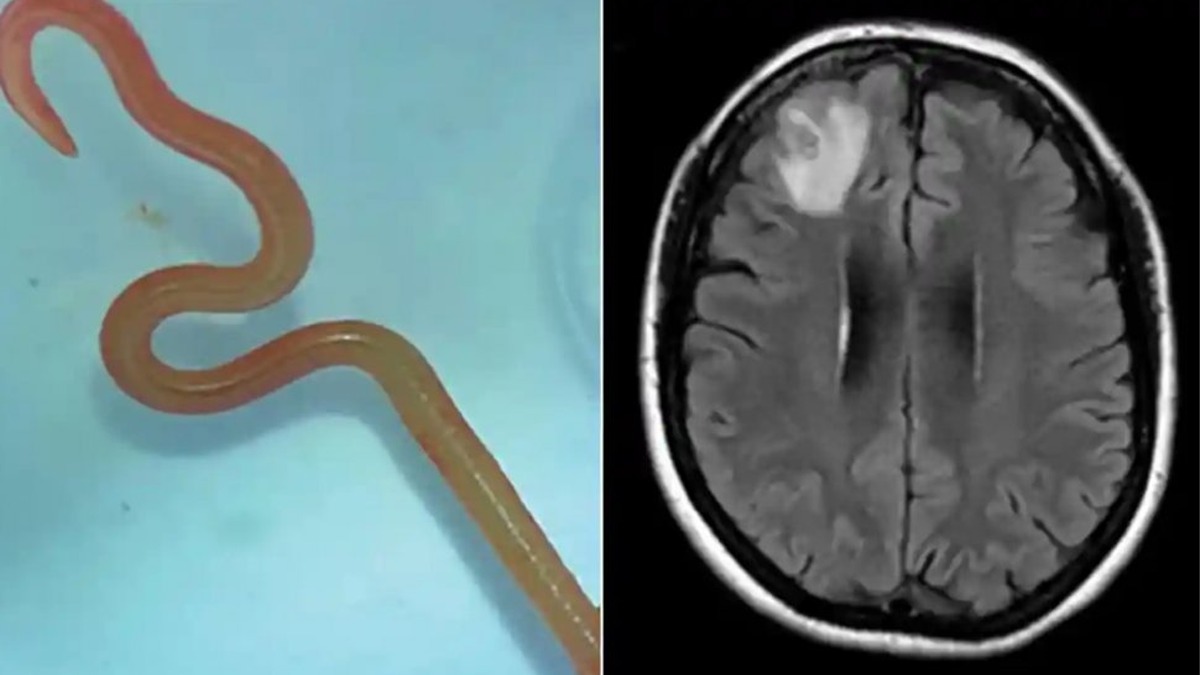

Un vierme care, de obicei, locuiește în pitoni, s-a aciuit în creierul unei femei. Parazitul viu, de 8 centimetri lungime, în acest caz, a fost găsit în cutia cranială a unei femei din Australia. “Ophidascaris robertsi”, pe numele lui, este un vierme rotund care locuiește de obicei în șerpii constrictori. Pacienta din spitalul din Canberra reprezintă primul caz din lume în care această creatură este descoperită în interiorul omului.

Pacienta, o femeie în vârstă de 64 de ani din sud-estul New South Wales, a fost internată pentru prima dată la spitalul local la sfârșitul lunii ianuarie 2021, după ce a suferit trei săptămâni de dureri abdominale și diaree, urmate de o tuse uscată constantă, febră și transpirații nocturne.

Până în 2022, simptomele ei au inclus și pierderi de memorie și depresie, ceea ce a dus la trimiterea ei la spitalul din Canberra. Un RMN la creier a dezvăluit anomalii…